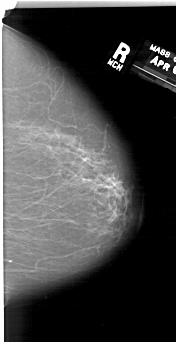

A_1192_1.RIGHT_CC

RIGHT_CC LINES 6496 PIXELS_PER_LINE 3331 BITS_PER_PIXEL 12 RESOLUTION 43.5 NON_OVERLAY